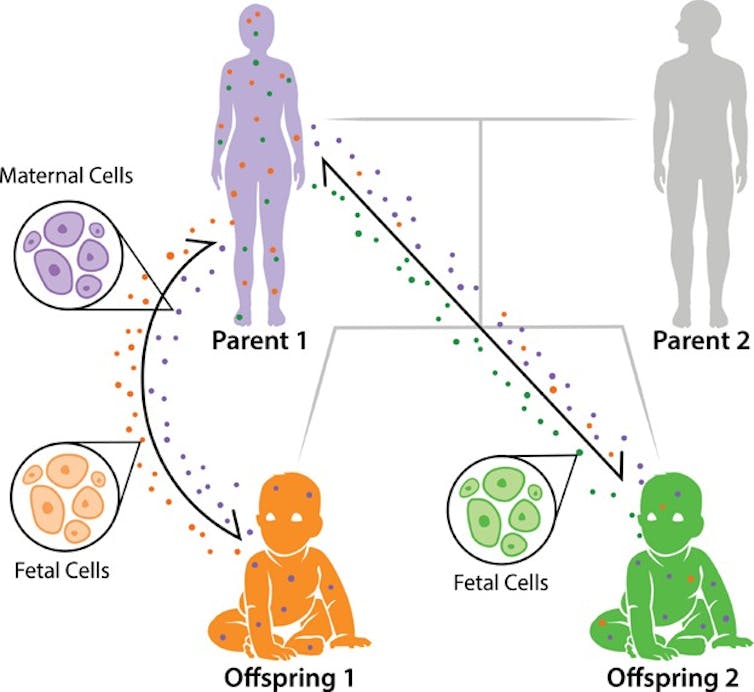

Durante el embarazo, se ha constatado que hay un flujo bidireccional de células entre la madre y el feto (incluso aunque haya un aborto) que da lugar a microquimerismo. Las funciones principales de este proceso, común entre mamíferos placentarios, parecen ser:

Este flujo es asimétrico: se transfieren más células del feto a la madre (microquimerismo fetal, originalmente descubierto en 1893) que viceversa (microquimerismo materno). Algunos de los muchos órganos humanos maternos donde pueden encontrarse células fetales son: la piel, los riñones, el hígado, la tiroides, las mamas (influyendo en la lactancia), los pulmones, el corazón y el cerebro.

Además, un planteamiento interesante revela que los hermanos y hermanas menores también podrían obtener células de sus hermanos y hermanas mayores. Esto ocurriría porque las células quedarían alojadas en el cuerpo de la madre y posteriormente serían transferidas a los sucesivos fetos.

Se ha demostrado que las células microquiméricas pueden permanecer en el cuerpo durante décadas, y puede que incluso de por vida. Si se supone que cualquier descendiente podría recibir células obtenidas por la madre durante su propia vida fetal, las probabilidades de albergar células de muchas personas en nuestro cuerpo aumentan considerablemente.